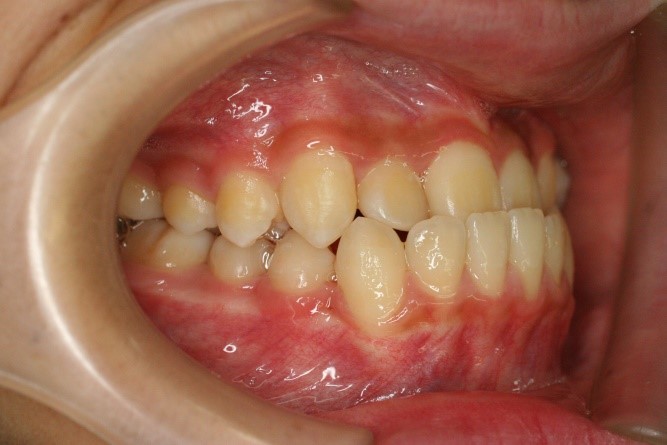

症例01|中学生の男子

前歯部の反対咬合

前歯部の反対咬合と上顎前歯のデコボコを主訴として来院されました。精査、診断の結果「前歯部に叢生を伴う反対咬合」と診断されました。

治療計画

非抜歯にて前歯の再配列、反対咬合の改善を行う事にしました。

治療前

• 右側

治療後

治療前の写真と比べると前歯部の反対咬合は改善されて、上顎の前歯部のデコボコも綺麗に並べる事ができました。

また口元は上の歯が前に出たために口唇がへこんでいたことも改善されて男らしい綺麗な口元に改善できました。 治療期間は2年と6か月を必要としました。